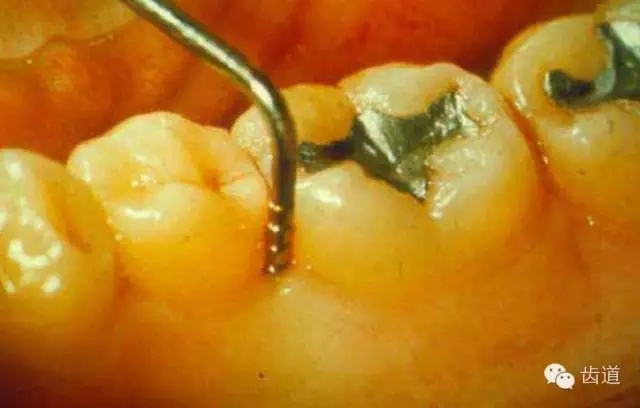

3、牙周袋探診

工具:牙周探針。其頂端為鈍頭,頂端直徑約0.5mm,探針上有刻度。

探診技術(shù):

A.握持探針的方法為改良握筆法

B.探診時(shí)要有支點(diǎn),可以是口內(nèi)支點(diǎn),也可以是口外支點(diǎn)。

C.探入時(shí)探針應(yīng)與牙體長(zhǎng)軸平行,頂端緊貼牙面,避開(kāi)牙石,直達(dá)袋底。

D.探入力量要輕,約為20-25g。

E.以提插方式移動(dòng)探針,如“走步”樣圍繞每個(gè)牙的每個(gè)牙面進(jìn)行探查,以發(fā)現(xiàn)袋最深的部位及袋的形態(tài)。

F.在探查鄰面時(shí),要緊靠接觸區(qū)處探入,探針可稍傾斜以便能探入接觸點(diǎn)下方的齦谷處。

G.全口牙齒探診時(shí),要按一定順序進(jìn)行。

探查的內(nèi)容及結(jié)果

探診深度:測(cè)量袋底至齦緣的距離,即為探診深度,以mm為單位記錄。

每個(gè)牙記錄六個(gè)部位:頰側(cè)近中、中央、遠(yuǎn)中及舌側(cè)近中、中央、遠(yuǎn)中位點(diǎn)。也可根據(jù)條件和需要,只記錄每個(gè)牙最探的位點(diǎn)。

牙周袋的檢查目的:

A.牙周袋的深度,袋的形態(tài)和范圍、根分叉有無(wú)受累

B.齦下牙石的多少及分布

C.有無(wú)根面齲

D.探診出血情況及膿性分泌物

牙周袋的檢查應(yīng)注意以下幾點(diǎn)

A.支點(diǎn)要穩(wěn),探針要緊貼牙面;

B.用力要適當(dāng);不能引起疼痛和損傷

C.探針要與牙體長(zhǎng)軸一致,檢查鄰面牙周袋時(shí),牙周探針靠著接觸點(diǎn)。

D.按一定的順序進(jìn)行。每個(gè)牙測(cè)定6個(gè)點(diǎn)